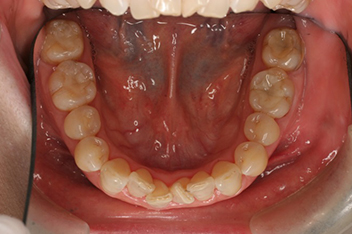

非抜歯のケース / 24歳(治療期間2年3か月)

部分矯正

わずかな重なりや、すき間など気になる部位だけを部分的な装置で改善します。

63歳(治療期間6か月)

下の前歯を一本抜歯して、部分矯正にて治療しました。見た目はもちろん、歯磨きがしやすくなるという大きなメリットもあります。